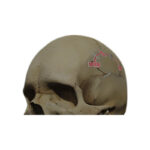

The first-in-human reconstruction for craniosynostosis with Osteomesh. Researchers estimate that about 1 in every 2,500 babies is born with craniosynostosis in the United States.

First-in-human patient specific implant with PCL-TCP for cranioplasty.

First-in-human for skull base with Osteomesh.